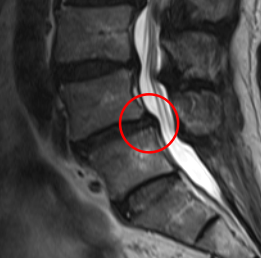

腰痛の原因を調べるため腰椎MRI画像を確認したところ、赤い枠内(L4/5)に椎間板ヘルニアが見つかりました。これが椎間板を圧迫して、腰痛が出てしまっていると考えられます。